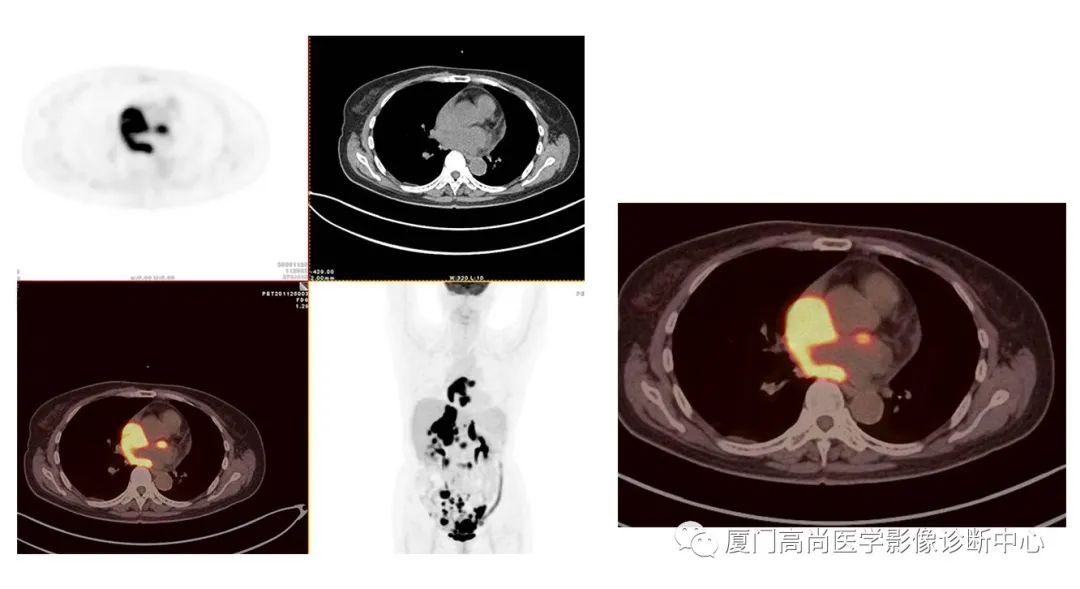

病例1:某男士,36歲,半年前摔傷,當(dāng)時無大礙,近幾個月來腰腿痛,并逐漸加重,消瘦10多斤。MRI檢查發(fā)現(xiàn)腰椎、骨盆 骨質(zhì)異常信號,查血各項腫瘤標(biāo)記物正常,因診斷不清而來做PET/CT檢查

淋巴瘤在骨骼、肝臟、脾臟、淋巴結(jié)表現(xiàn)

肝臟、脾臟、骨骼淋巴瘤病灶

骨骼、腋窩淋巴結(jié)病灶

PET/CT發(fā)現(xiàn) :全身多發(fā)淋巴結(jié)腫大,F(xiàn)DG攝取增高;肝臟、脾臟多發(fā)低密度結(jié)節(jié), FDG攝取增高;雙側(cè)扁桃體腫大,F(xiàn)DG攝取增高;全身多處骨骼破壞,F(xiàn)GD攝取增高;上述考慮為淋巴瘤

經(jīng)淋巴結(jié)穿刺活檢 :病理診斷為彌漫大B細(xì)胞淋巴瘤